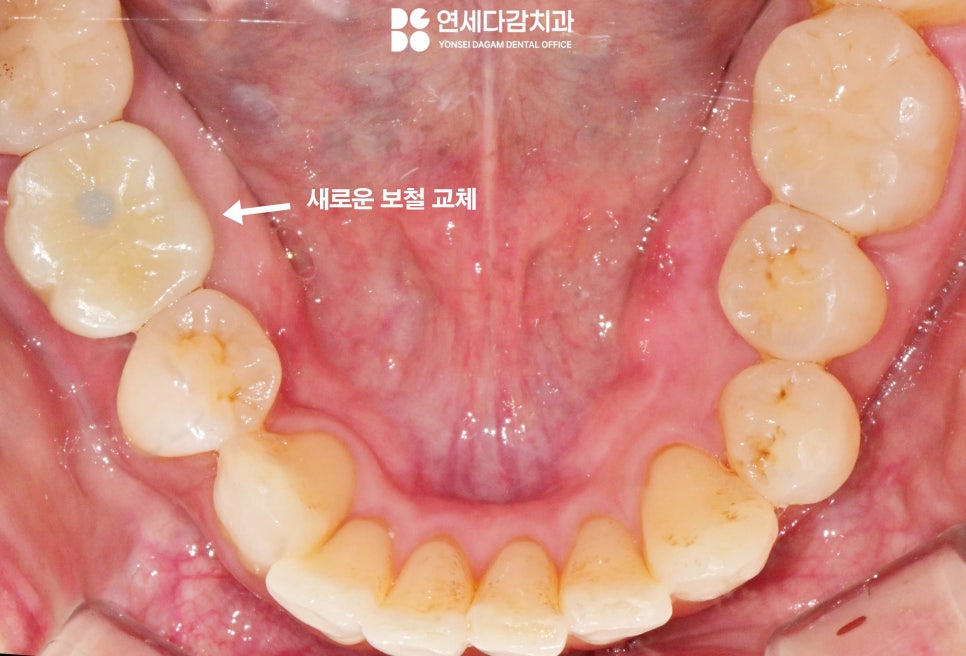

거여역 치과 에서 보여드린 증례는

다행히도 두 번째 방법을 이용하여

얇은 잇몸 치료 전용 팁을

장착하여 진동을 줬을 때

잘 빠진 모습입니다.

내부 모습도 나사 일부가

잘 빠져나온 것을 확인한 뒤

이후 새로운 보철물을 제작하여

기능을 회복할 수 있습니다.